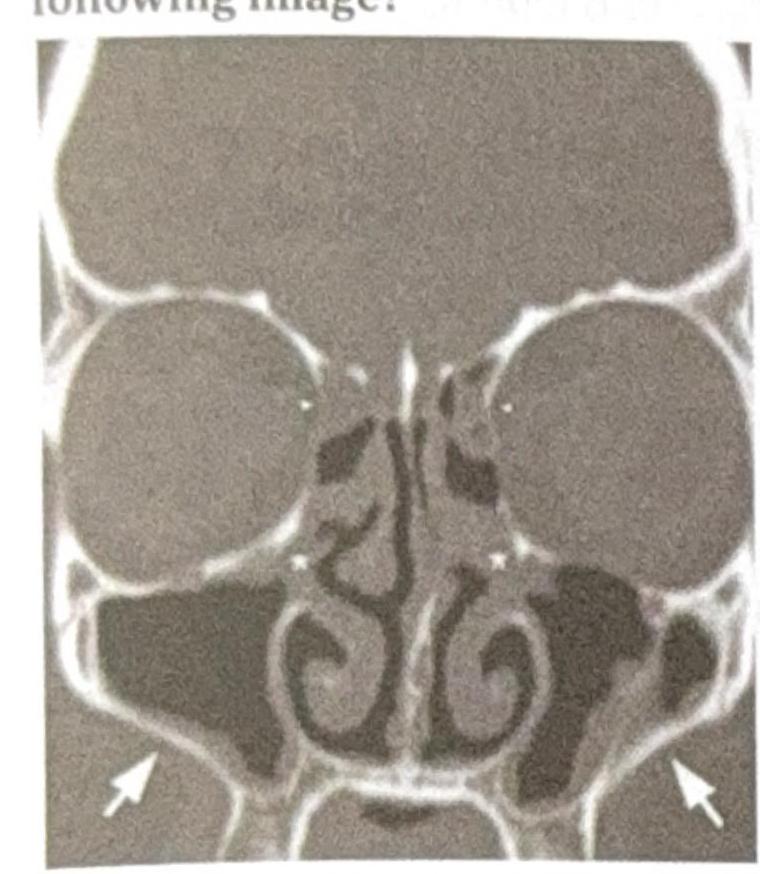

Which sinus drainage is impaired in the following image?

Explanation: ***Maxillary*** - The image shows **arrows pointing to the maxillary sinuses** with visible **opacification and fluid accumulation**, indicating **impaired drainage**. - Maxillary sinuses drain through the **ostiomeatal complex** into the middle meatus; obstruction leads to mucus retention and sinusitis. *Ethmoid* - The **ethmoid air cells** located between the eyes, medial to the orbits, do not show significant **opacification** or drainage impairment. - These complex honeycomb-like structures appear **relatively clear** without evidence of fluid accumulation. *Sphenoid* - The **sphenoid sinuses** located deeper in the skull, behind the ethmoid sinuses, are **not prominently affected** in this image. - No significant **opacification** or mucosal thickening visible to suggest impaired drainage. *Frontal* - The **frontal sinuses** located above the eyebrows appear **relatively clear** without significant opacification or drainage impairment. - These sinuses drain through the **frontonasal duct** and do not show evidence of fluid retention in this image.